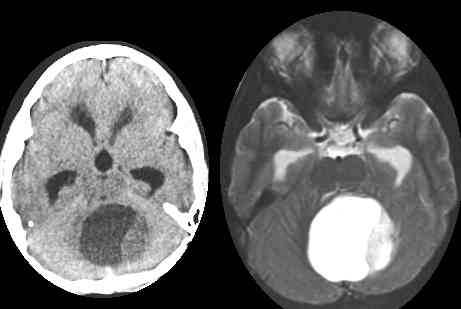

小脑肿瘤即是生长在小脑部位的脑肿瘤。小脑是颅内占位性病变(颅内肿瘤)的好发区,成人和儿童均可发生,常见肿瘤为星形细胞瘤、髓母细胞瘤、血管母细胞瘤、室管膜瘤等。不同的小脑肿瘤恶性程度不同,治疗方法和预后亦不同,术前正常诊断对治疗方案的制定和判断预后有重要临床意义。

2、髓母细胞瘤:起源于髓母细胞,与胚胎期髓上皮二代原始小细胞形态相似,具有双向分化特征,既向神经细胞又向胶质细胞方向分化。儿童多见于小脑蚓部,成人则多位于小脑表面。主要见于15岁前,由 其4-8岁间较常见。另一个高峰年龄在25岁左右。髓母细胞瘤多为实性,类圆形或不规则形,边界较清楚,内部可出现囊变,少见出血及钙化。